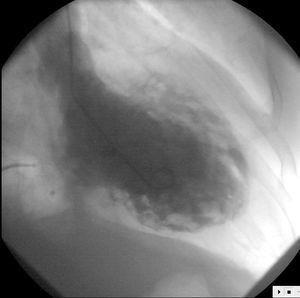

Como parte del protocolo de estudio de las taquicardias ventriculares (TV), con sospecha clínica de miocardiopatía dilatada, se le realizó un estudio hemodinámico. La ventriculografía izquierda mostró un ventrículo con fracción de eyección (FE) del 20%, con defectos generalizados de la contractilidad y con una imagen de importante trabeculación que sugirió el diagnóstico de miocardiopatía no compactada (MNC) o miocardiopatía espongiforme (ME) (fig. 1). No se detectó insuficiencia mitral angiográficamente significativa. En el cateterismo derecho las presiones fueron: aurícula derecha (AD) 10 mmHg, ventrículo derecho (VD) 70/4 mmHg, arteria pulmonar (AP) 70/15 mmHg, enclavamiento capilar pulmonar (PECP) 15 mmHg. Índice cardíaco 2 litros/minuto/m2; presión telediastólica VI (PTDVI) 30 mmHg; gradiente mitral invertido (PTDVI > PECP). La coronariografía mostró unas arterias epicárdicas angiográficamente normales.

Figura 1. Ventriculografía izquierda (proyección oblicua anterior derecha) que muestra en diástole una cámara dilatada con un llamativo aspecto esponjoso del miocardio ventricular.